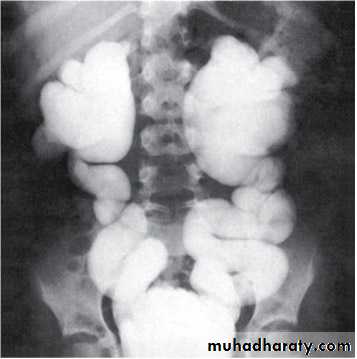

Grading of VUR

The degree of reflux is graded I–V.Grading is based on the appearance of contrast agent in the collecting system during voiding cystourethrography (VCUG(.

Hydroureteronephrosis(1) Increased work load

(2) High hydrostatic pressure

(3) Weak ureteral musculature

The VCUG:

the definitive examination

to diagnose and grade reflux and establish reversible causes

must include a voiding phase:

in some cases, reflux may be seen only during the elevated intravesical pressures associated with micturition.

in visualizing the urethra, may allow the diagnosis of outflow obstruction to be made (e.g., posterior urethral valves).